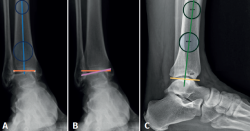

En la proyección anterior de tobillo evaluaremos el talar tilt o ángulo de inclinación del astrágalo, aumentado en las lesiones incongruentes intraarticulares (Figura 1).

Figura 1. A: ángulo tibial distal anterior, entre el eje anatómico de la tibia en el plano posteroanterior y la línea de la superficie articular distal de la tibia; B: ángulo de inclinación astragalina (talar tilt), formado entre la línea de la superficie articular tibial y la línea de la superficie articular astragalina. Evalúa la congruencia articular; C: ángulo tibial distal lateral, entre el eje anatómico lateral de la tibia y la línea de la superficie articular distal lateral de la tibia.